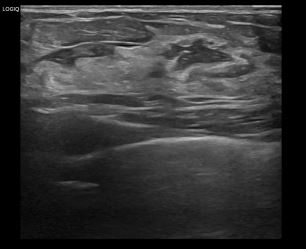

상기환자는 좌측유방 분비물로  내원하신 40대중반

여성분으로 의심스러운 좌측혹 조직검사 시행해 상피내암 으로 진단되었습니다